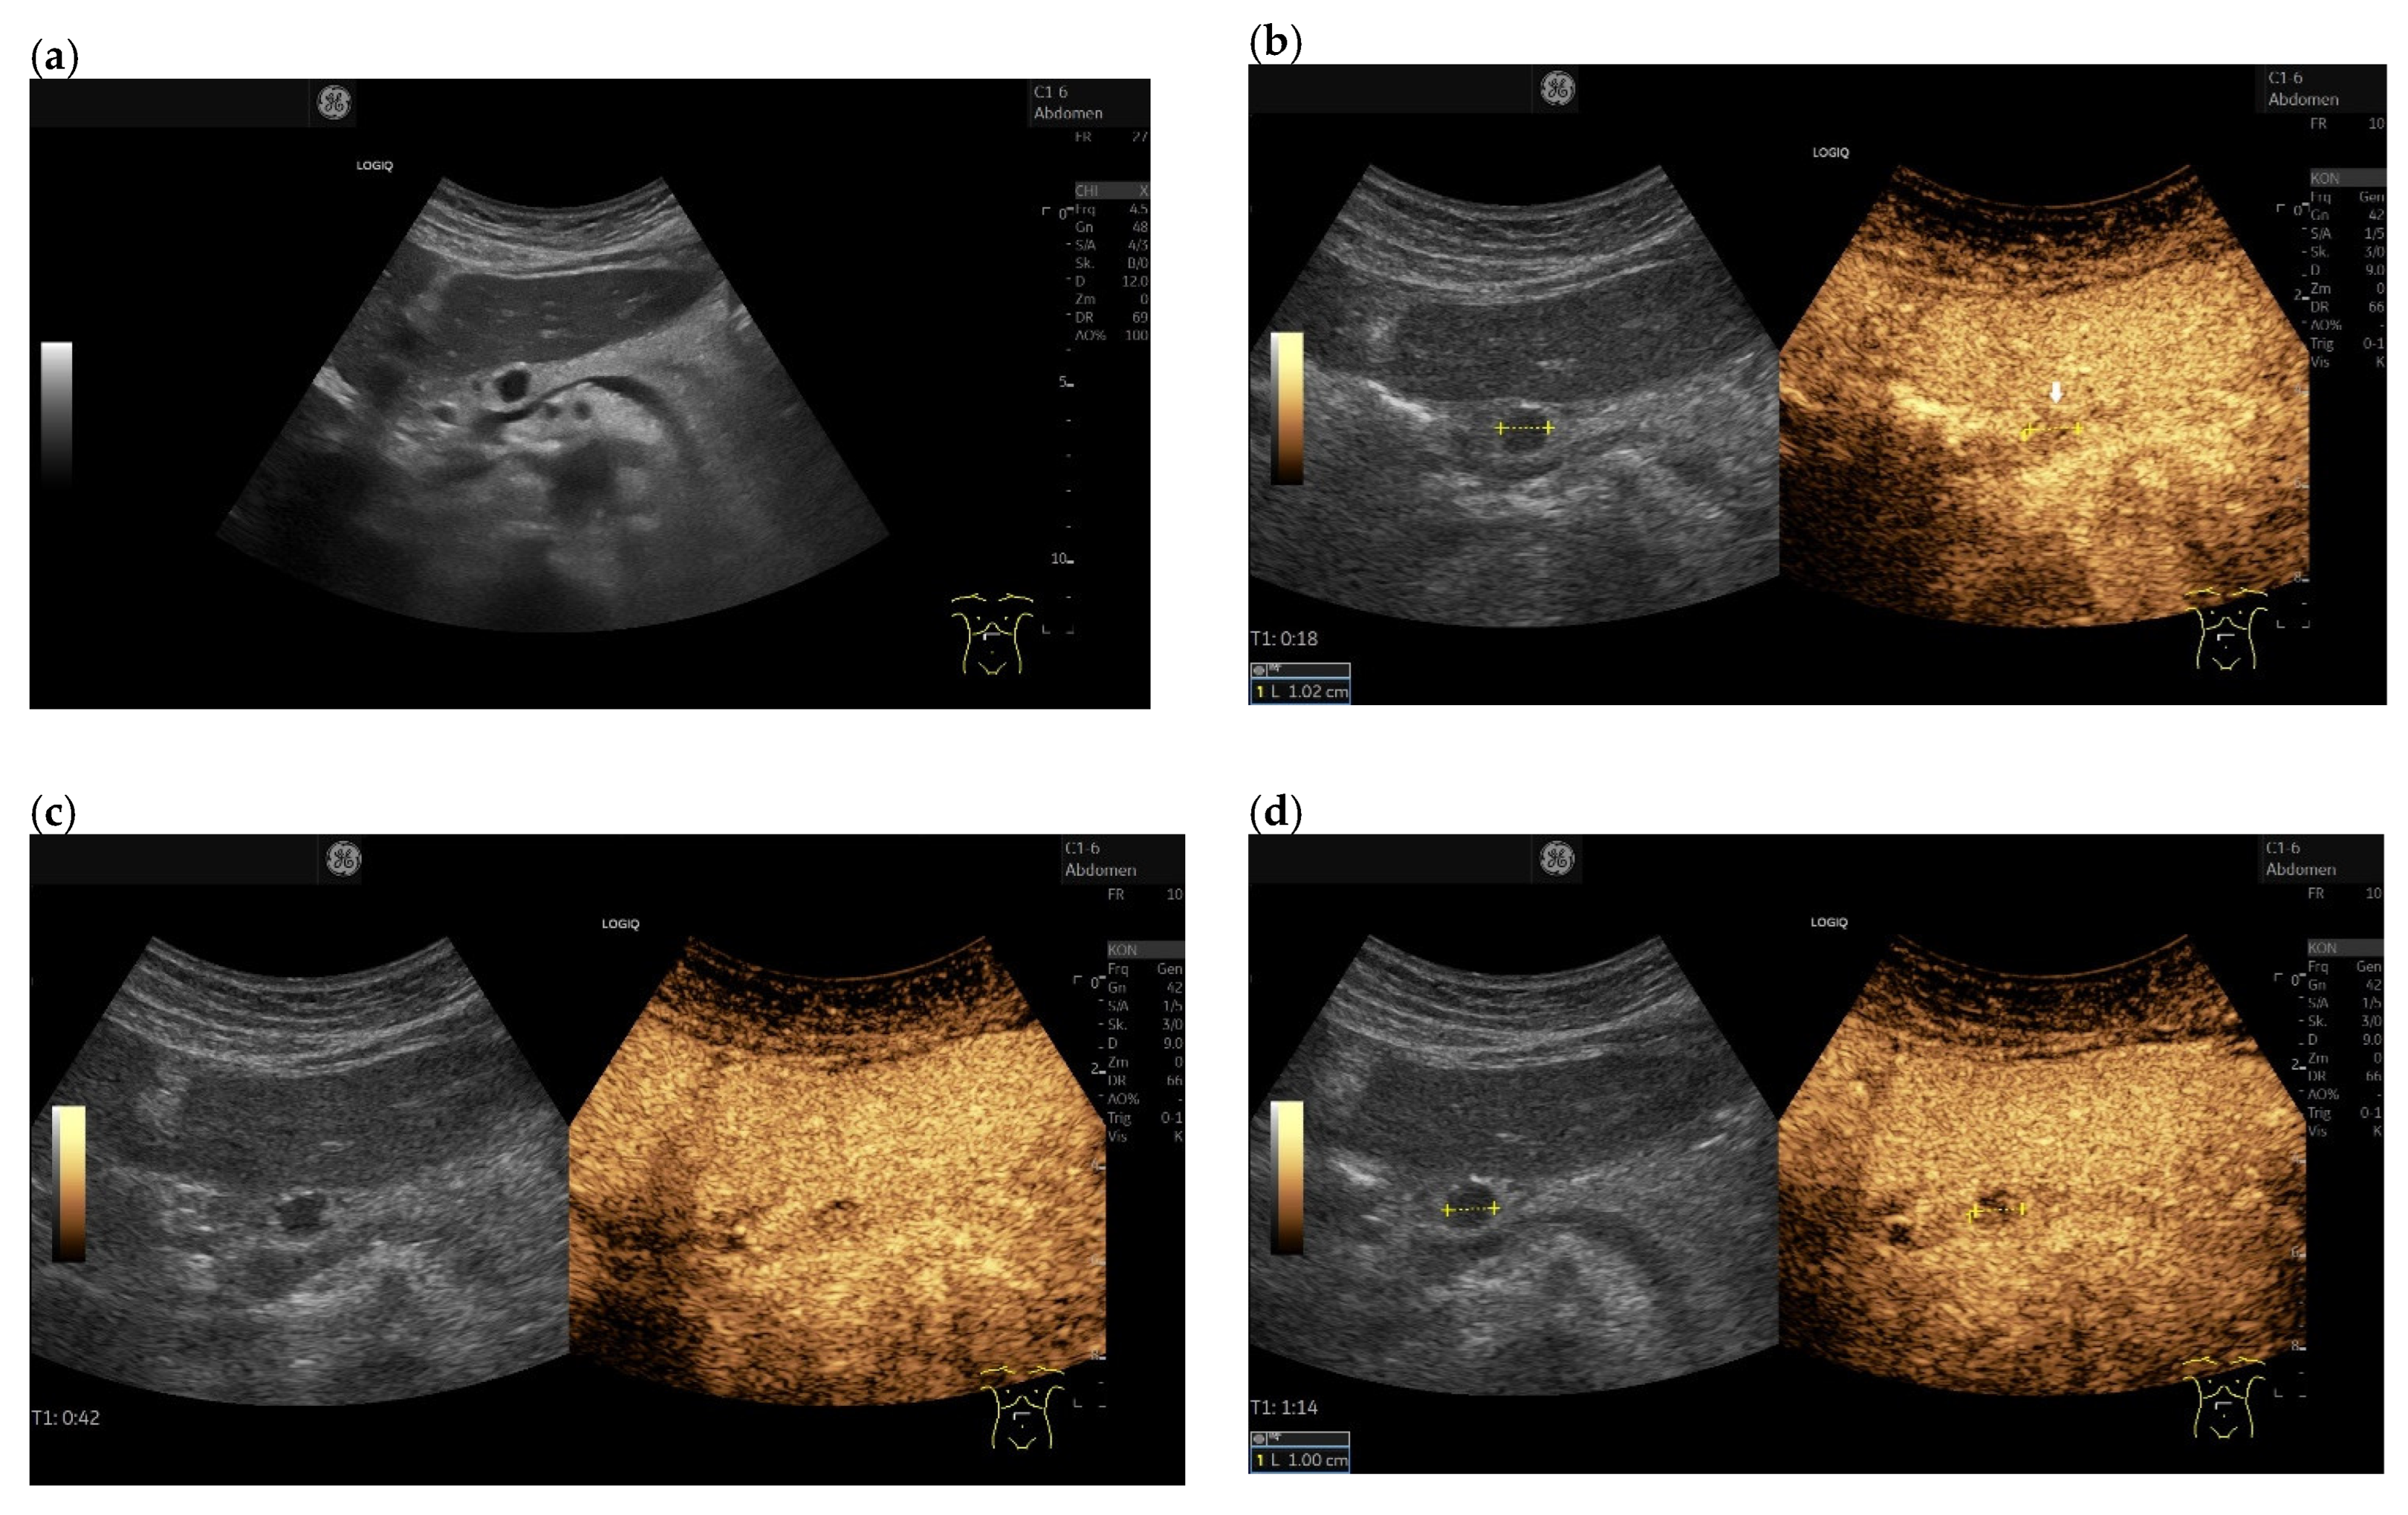

3.4. CEUS and CH-EUS

B-mode US/EUS

| Mostly hypoechoic, homogeneous, or heterogeneous More likely well-defined borders (46%) Anechoic and hyperechoic lesions are possible | Hypoechoic, typically heterogeneous, irregular borders | Hypoechoic, mostly homogeneous, smoothly bordered. Cystic components or cystic solid PanNENs are possible |

| Variable, in 80% no pancreatic duct dilatation | Pancreatic duct stenosis and pancreatic duct dilatation are an early and typical feature | No pancreatic duct dilatation |

| Mostly no infiltration into adjacent vessels | Infiltration around and into the vessels | No infiltration into adjacent vessels |

| Colour Doppler Imaging | RCC metastases are hypervascularized Most other pancreatic metastases are hypovascularized | No hypervascularization | Hypervascularized |

| RCC metastases [83] (n = 4) | Hyperenhancement, Early | Hyperenhancement | ||

| RCC metastases [61] (n = 3) | Hyperenhancement, homogeneous pattern | Slow washout | ||

| RCC metastasis [86] (n = 1) | Hyperenhancement, Inhomogeneous pattern | No washout | ||